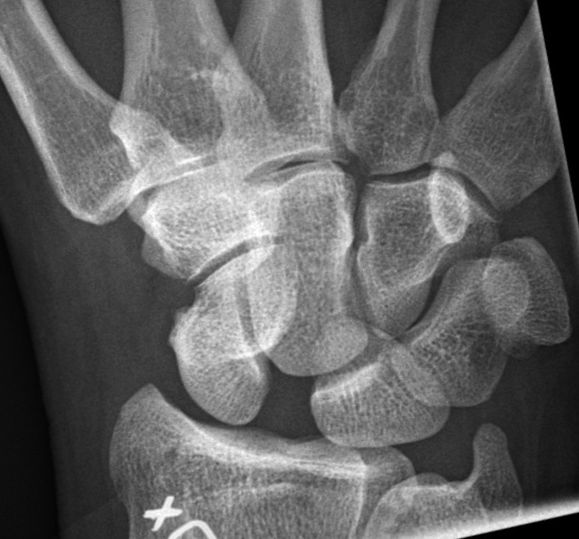

- Ökat avstånd mellan skafoideum och lunatum på frontalbild av handled. Ska normalt vara < 3 mm, > 5 mm är patologiskt. Men detta visas på röntgen först 3-4 månader efter skada. [2]

Ökat avstånd mellan skafoideum och lunatum vid ulnardeviation